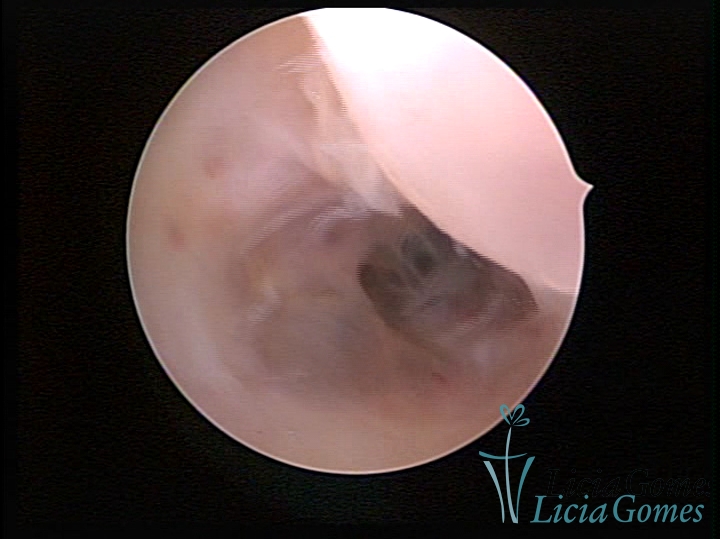

Sinéquia TIPO FIBROSA

As Sinéquia uterinas são cicatrizes (aderências) entre as superfícies das paredes uterinas, que podem ocorrer após manipulação cirúrgica, ou curetagem uterina, ou após um processo inflamatório na cavidade uterina (endometrite), podendo levar a alterações menstruais, infertilidade, e complicações obstétricas, como abortamento, parto prematuro.